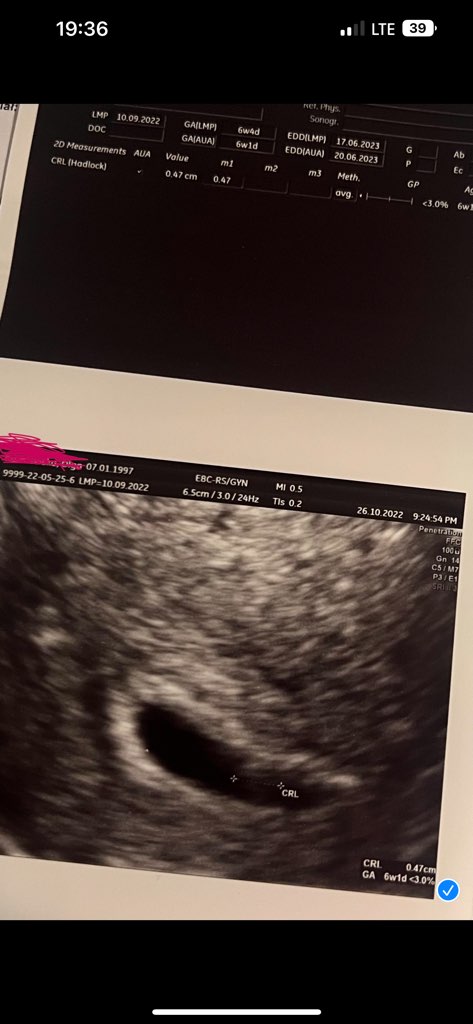

Widziałam serduszko ✊🏼 dr powiedział ze wszystko wyglada dobrze, w piątek mam przyjść dosłownie na 3 min na usg zobaczyć czy płód rośnie.

• IMG_3051.jpeg

IMG_3051.jpeg

58,1 KB · Wyświetleń: 122